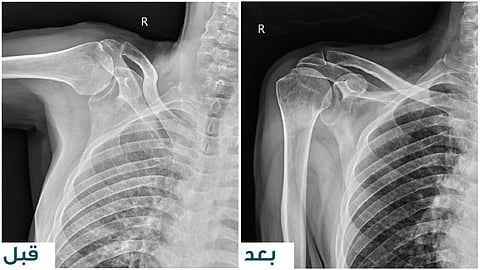

بدأت رحلة العلاج حينما راجع المريض عيادة جراحة الأطراف العلوية ، وأظهرت الفحوصات وجود تمزُّقٍ كاملٍ في جميع عضلات الكتف، وخشونةٍ شديدةٍ في المِفصَل؛ مما جعل التدخُّل الجراحيَّ الخيار الأفضل لضمان استعادة الوظيفة الحركية للمريض.

وبناءً على التقييم ، قرَّر الفريق الطبي إجراء عملية استبدال مِفصل الكتف المقلوب، وهي تقنيةٌ جراحيةٌ متقدِّمةٌ مصمَّمةٌ خصِّيصًا لعلاج الحالات التي تعاني تلف العضلات الدوّارة والخشونة المتقدِّمة في المِفصل.

وقد تمَّ تنفيذ العملية بنجاحٍ تامّ، وبدون أي مضاعفات ، وخضع بعدها إلى برنامج علاجٍ طبيعيٍّ مكثَّف لمدة ثلاثة أشهر، تحت إشراف فريقٍ متخصِّص في التأهيل الحركي.

بعد إنتهاء المريض من البرنامج، استعاد المريض كامل حركة الكتف دون ألمٍ أو أيِّ قيودٍ وظيفية؛ مما يعكس نجاح الجراحة والتأهيل الطبي المتطوِّر الذي حصل عليه.